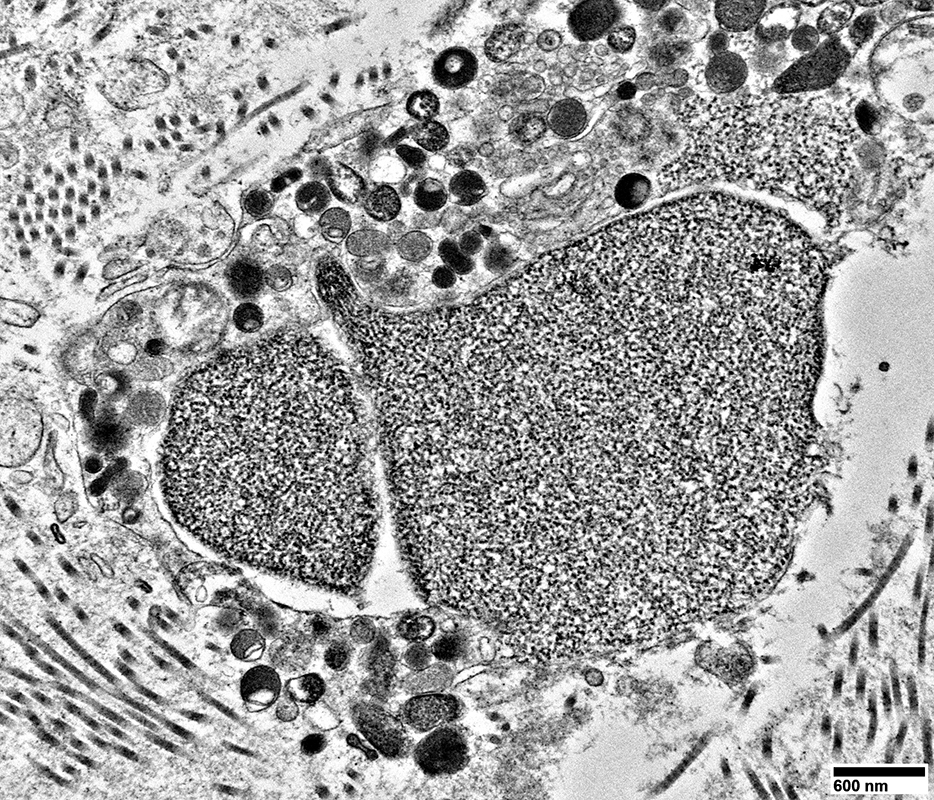

Regenerating Axons

Clusters of processes

2 types of contents

Tubulovesicular profiles

Densely distributed in axon processes

Compare to:

Axons, large & proximal to nerve lesion

Organelles, including many mitochondria

No surrounding Schwann cell cytoplasm

From: R Schmidt